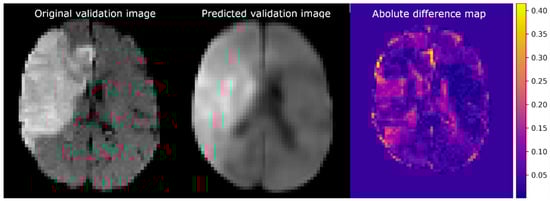

3.2. Autoencoder Image Reconstruction